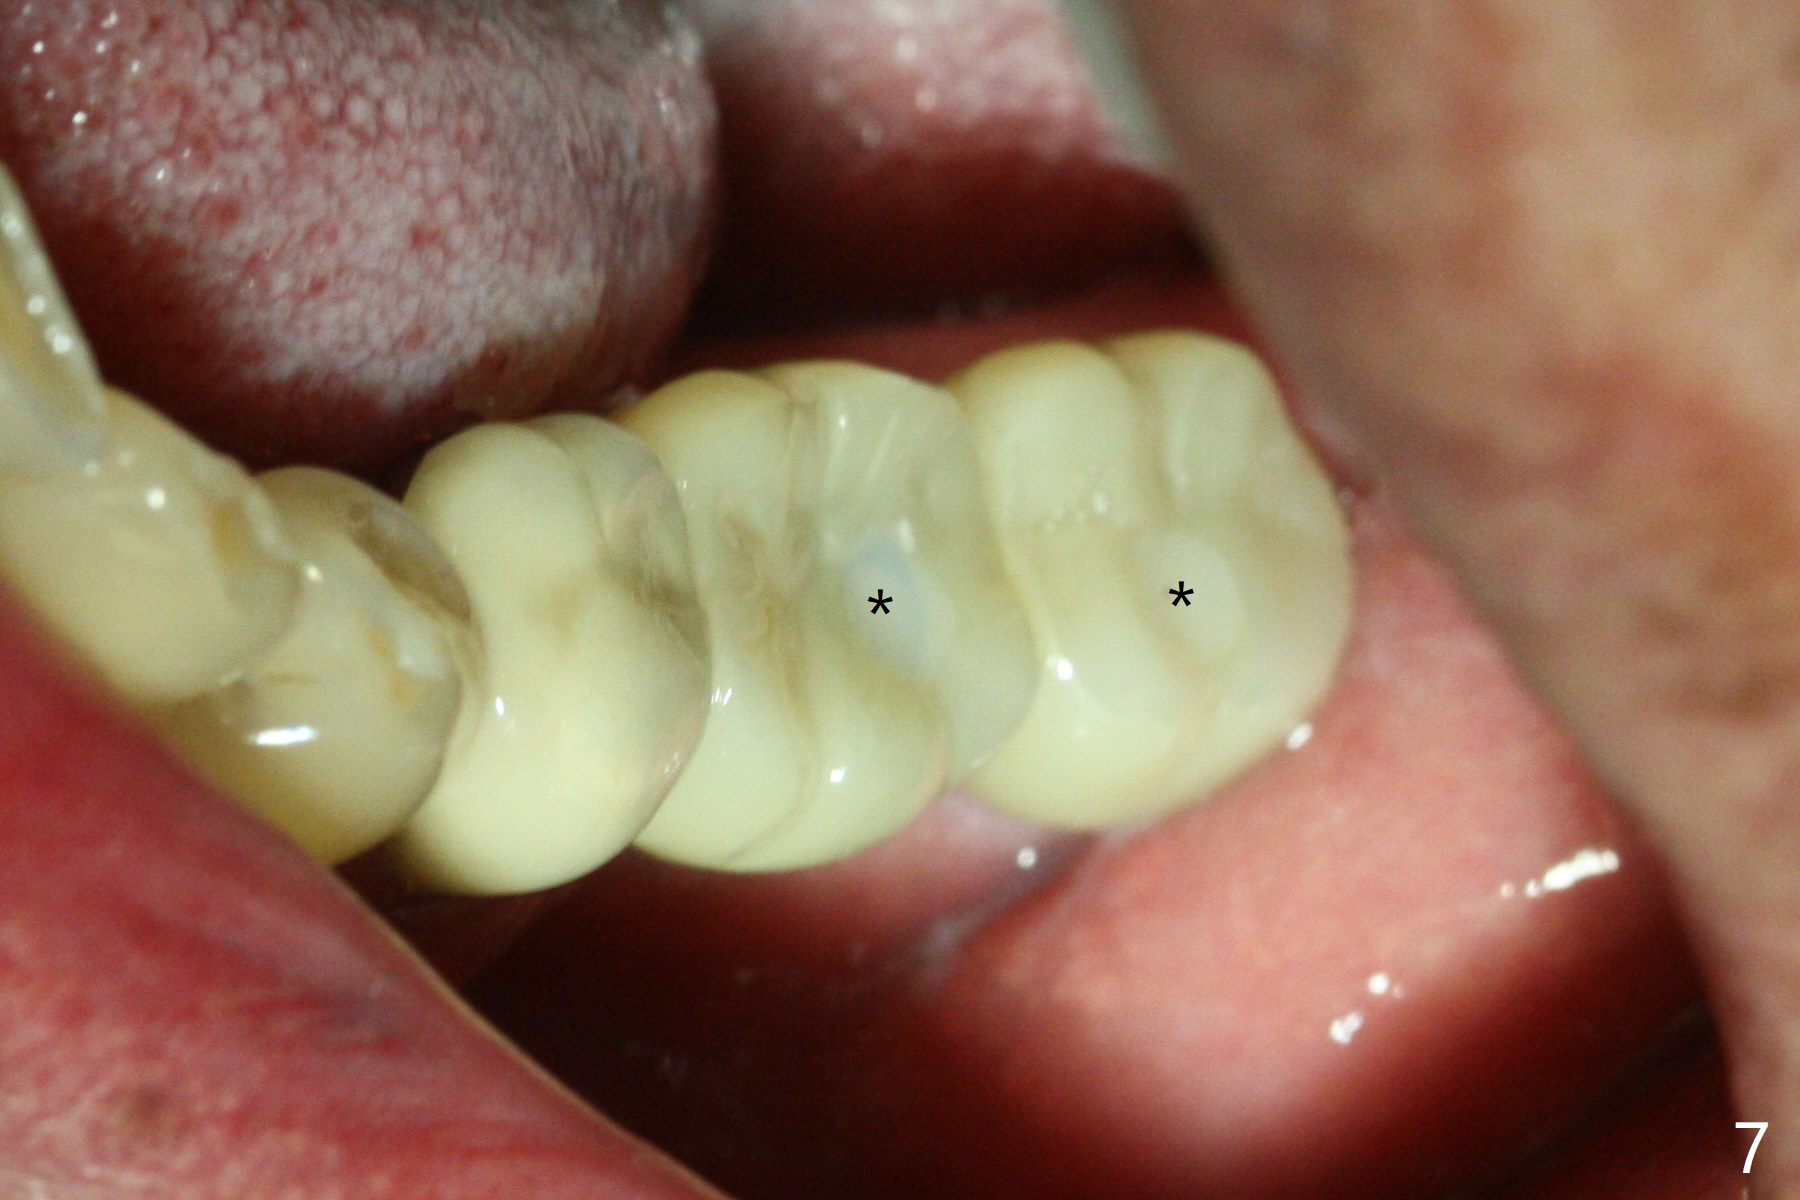

A drawback of placing an implant in the distal socket of the 2nd lower molar is closer to the Inferior Alveolar Canal. The implants seem to have osteointegrated 4.5 months postop (Fig.5). While the ridge at #19 appears to be wider than preop (as compared to Fig.1), that at #18 seems to be atrophic 5 months postop (Fig.6 * (1 week post cementation)). The distal implant placement at #19 may increase possibility of abutment screw loosening during functioning (Fig.7 *). When the patient returns for periodic exam 1.5 months post cementation, loose contact between the implant crowns is noted (Fig.8). The bony trabeculae form between the 2 implants crestally 12 months postop, i.e., 7 months post cementation (Fig.9). The loose contact between the 2 implants is corrected 14 months post cementation.